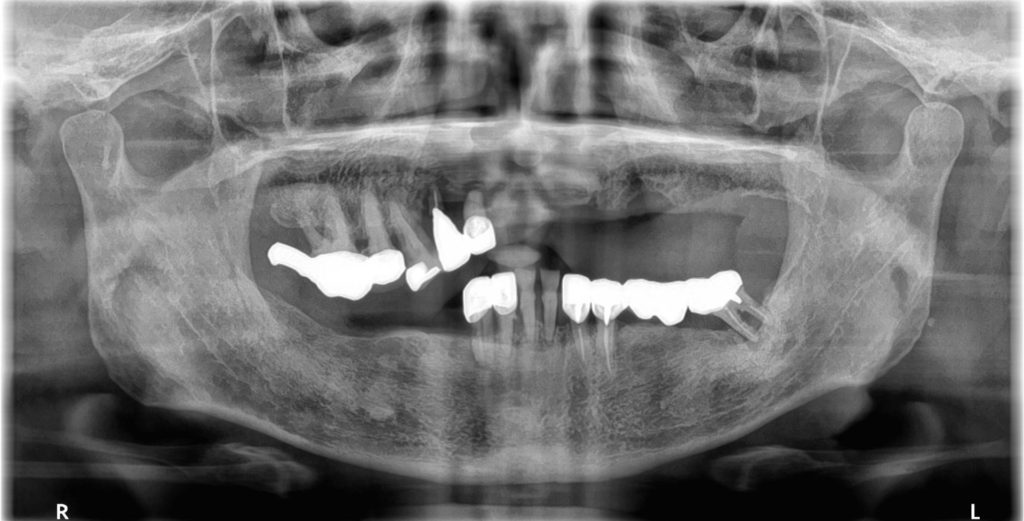

初診時の様子

前歯がかなり動いていますね。これは噛むたびに負担がかかっているのが原因かも知れません。他にも、右下には歯がなく、入れ歯を作られたけど痛くて使えなかったとのことですね。

インプラントはご自身の歯のようにしっかり噛める利点がありますが、まずはインプラントが可能な状態かどうか、精密検査をして判断しましょう。

はい。その通りです! まずはCT撮影などの精密検査をして、骨の状態や噛み合わせを詳しく確認しましょう。それで、最適な治療計画を立てることができます。